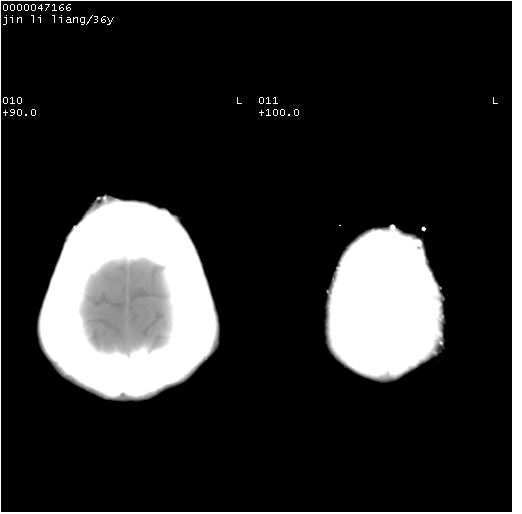

患者 男,36岁。头面部“土炮”炸伤。pe:面目全非,伤口流血不止。

临床诊断:头面部外伤。

颅脑ct轴位平扫(层厚、层距均为10mm),图像如下:

左眼球内容物浑浊其内见气体影,头面部异物.

左眼球破裂积气并异物,眶周、额顶部头皮及软组织挫伤并异物!

迎面一炮,满脸开曝。额顶部头皮及软组织挫伤并异物,左眼球破裂积气并异物,典型的面目全非,惨不忍睹。

1左侧眼球破裂并积气,球内、框内异物。

2额部顶部软组织伤。